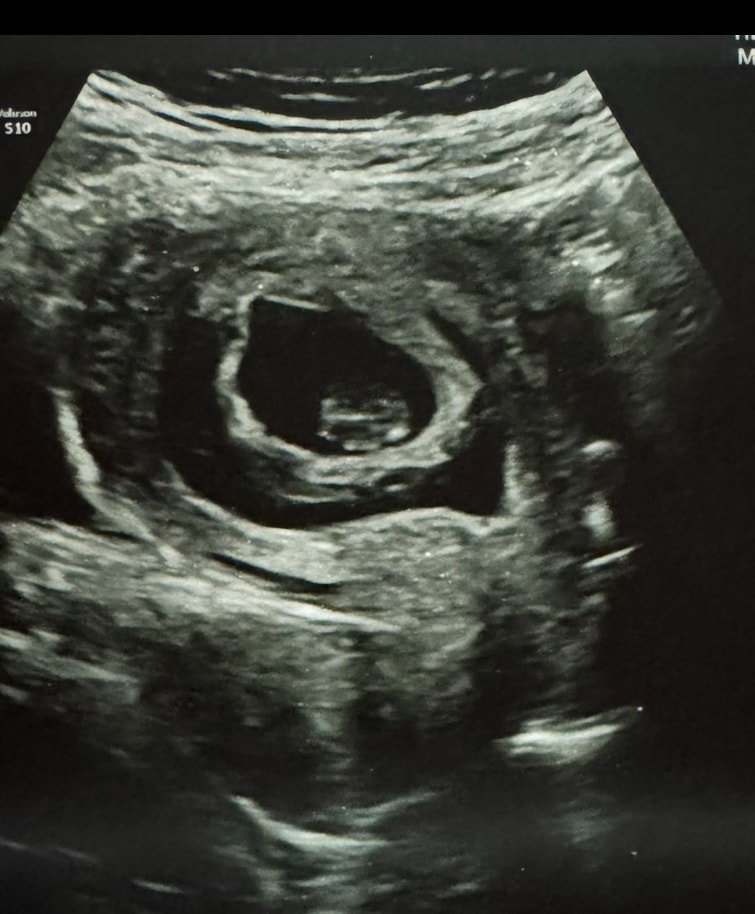

Нашла УЗИ, понизу темный полукруг вокруг центрального «круга» это все отслойка. Ну частично прижился. Всю беременность кровило, если коротко.